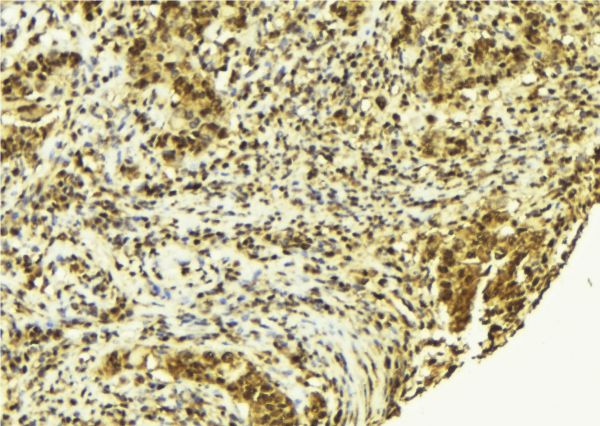

IHC (Immunohistochemistry)

(AAA327375 at 1/100 staining Human breast cancer tissue by IHC-P. The sample was formaldehyde fixed and a heat mediated antigen retrieval step in citrate buffer was performed. The sample was then blocked and incubated with the antibody for 1.5 hours at 22 degree C. An HRP conjugated goat anti-rabbit antibody was used as the secondary.)